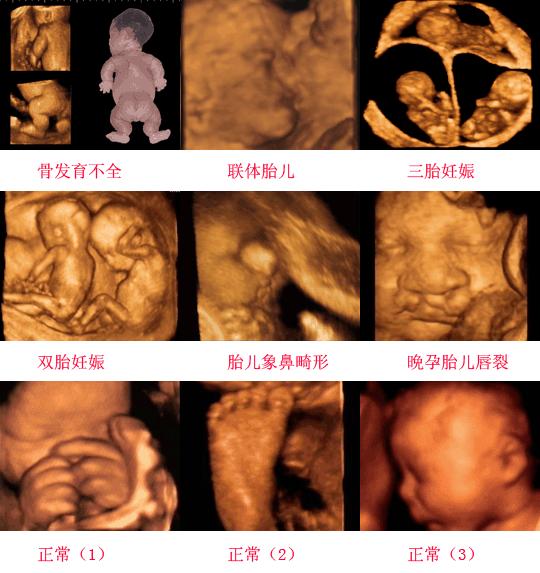

到28周的时候医生让我做个B超检查宝宝发育情况,做B超用的时间好长,当时心里很忐忑,时间越长就意味着越有情况。果不其然,医生告诉我其他都好,宝宝稍微偏小,但是嘴唇看不清,让我过一个星期复查。当时听到这个整个人就不好了,要是宝宝是兔唇怎么办,医生还怪我没有去做四维。我回家告诉家里人说其他都好,就是胎儿嘴唇看不清?我爸一听是在家里的县医院做的B超,根本就不相信。直接说这次检查没事,家里这边检查本来就没有什么技术含量。可即使如此,我还是很担心,那一周心情很不好。

我回自己家后,就让老公休息时陪我去市里医院检查。跟市里医院的妇产科医生说了在家里检查嘴唇看不清,问能不能帮我看下。医生就问我几个月了?我说7个月。“都7个月了啊,胎儿越大,羊水越少,做B超看不清很正常的,就是我们这边也不是每次都能看清楚。有时候一次就能看到,有时候连续好几次都看不到的,这种情况不用担心,一般不会有问题的,现在也不用检查。”然后,我就啥也没有检查就回家了。可宝宝不出生,我依然担心,心情很低落。我后来自己劝自己,总是心情不好这样会对宝宝不利,况且已经7个月了,也舍不得流掉,那就生下来吧,大不了花钱给她看病。慢慢的调整自己的心态,每天陪着大宝玩,嘻嘻哈哈的数着日子过。